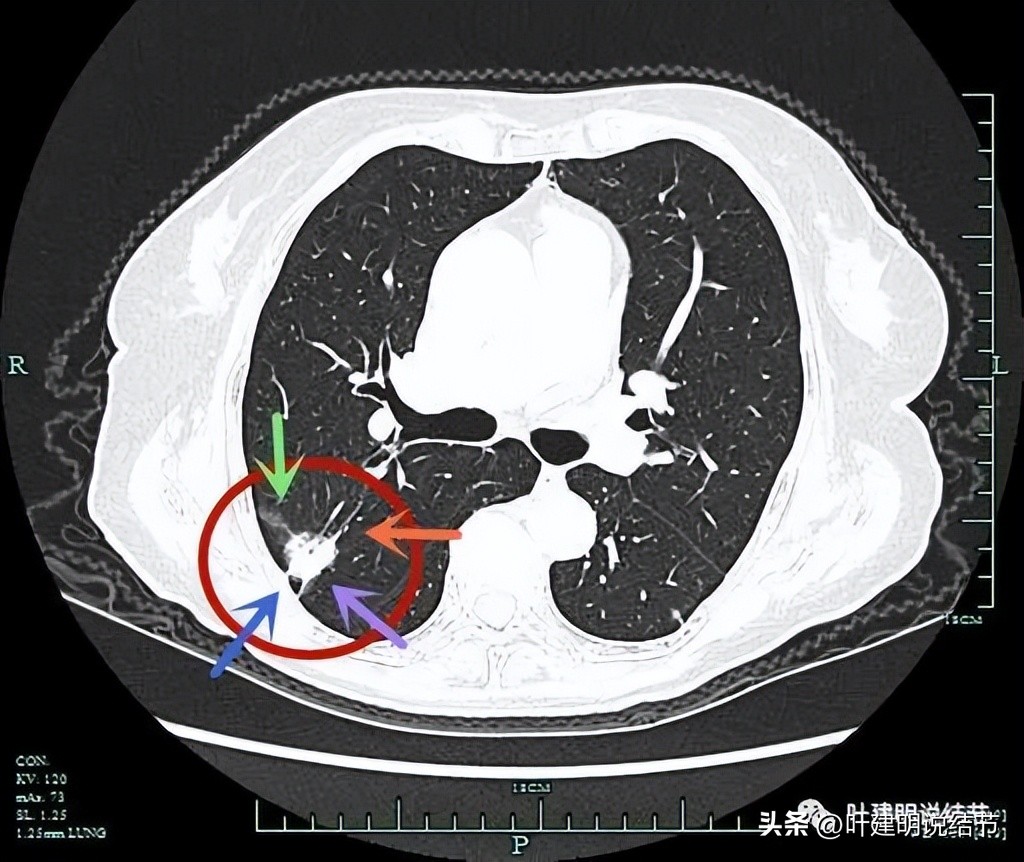

病灶出现,实性,有微小血管进入。

微小血管进入(桔色箭头),胸膜略有牵拉(蓝色箭头)。

病灶边缘区域有磨玻璃成分,但磨玻璃成分的边界显得有些模糊(绿色箭头)。

病灶有支气管截断(黄色箭头);边缘区域磨玻璃成分(绿色箭头);胸膜牵拉(蓝色箭头)。

上图层面有些像混合磨玻璃密度,血管进入病灶明显(桔色箭头);胸膜牵拉(蓝色箭头);边缘似略见细小毛刺,但很细小(紫色箭头)。